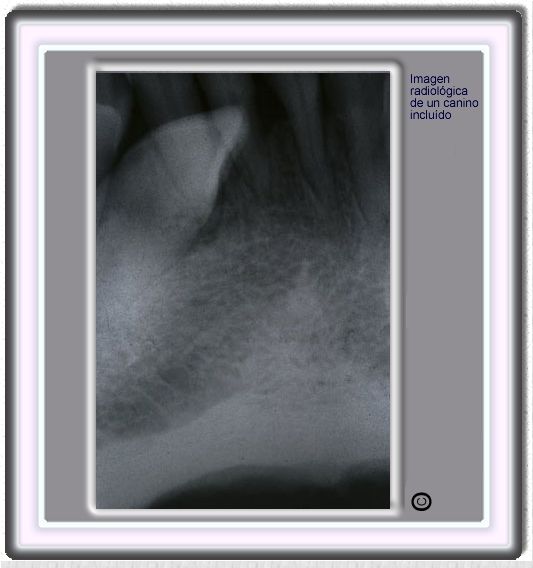

image420